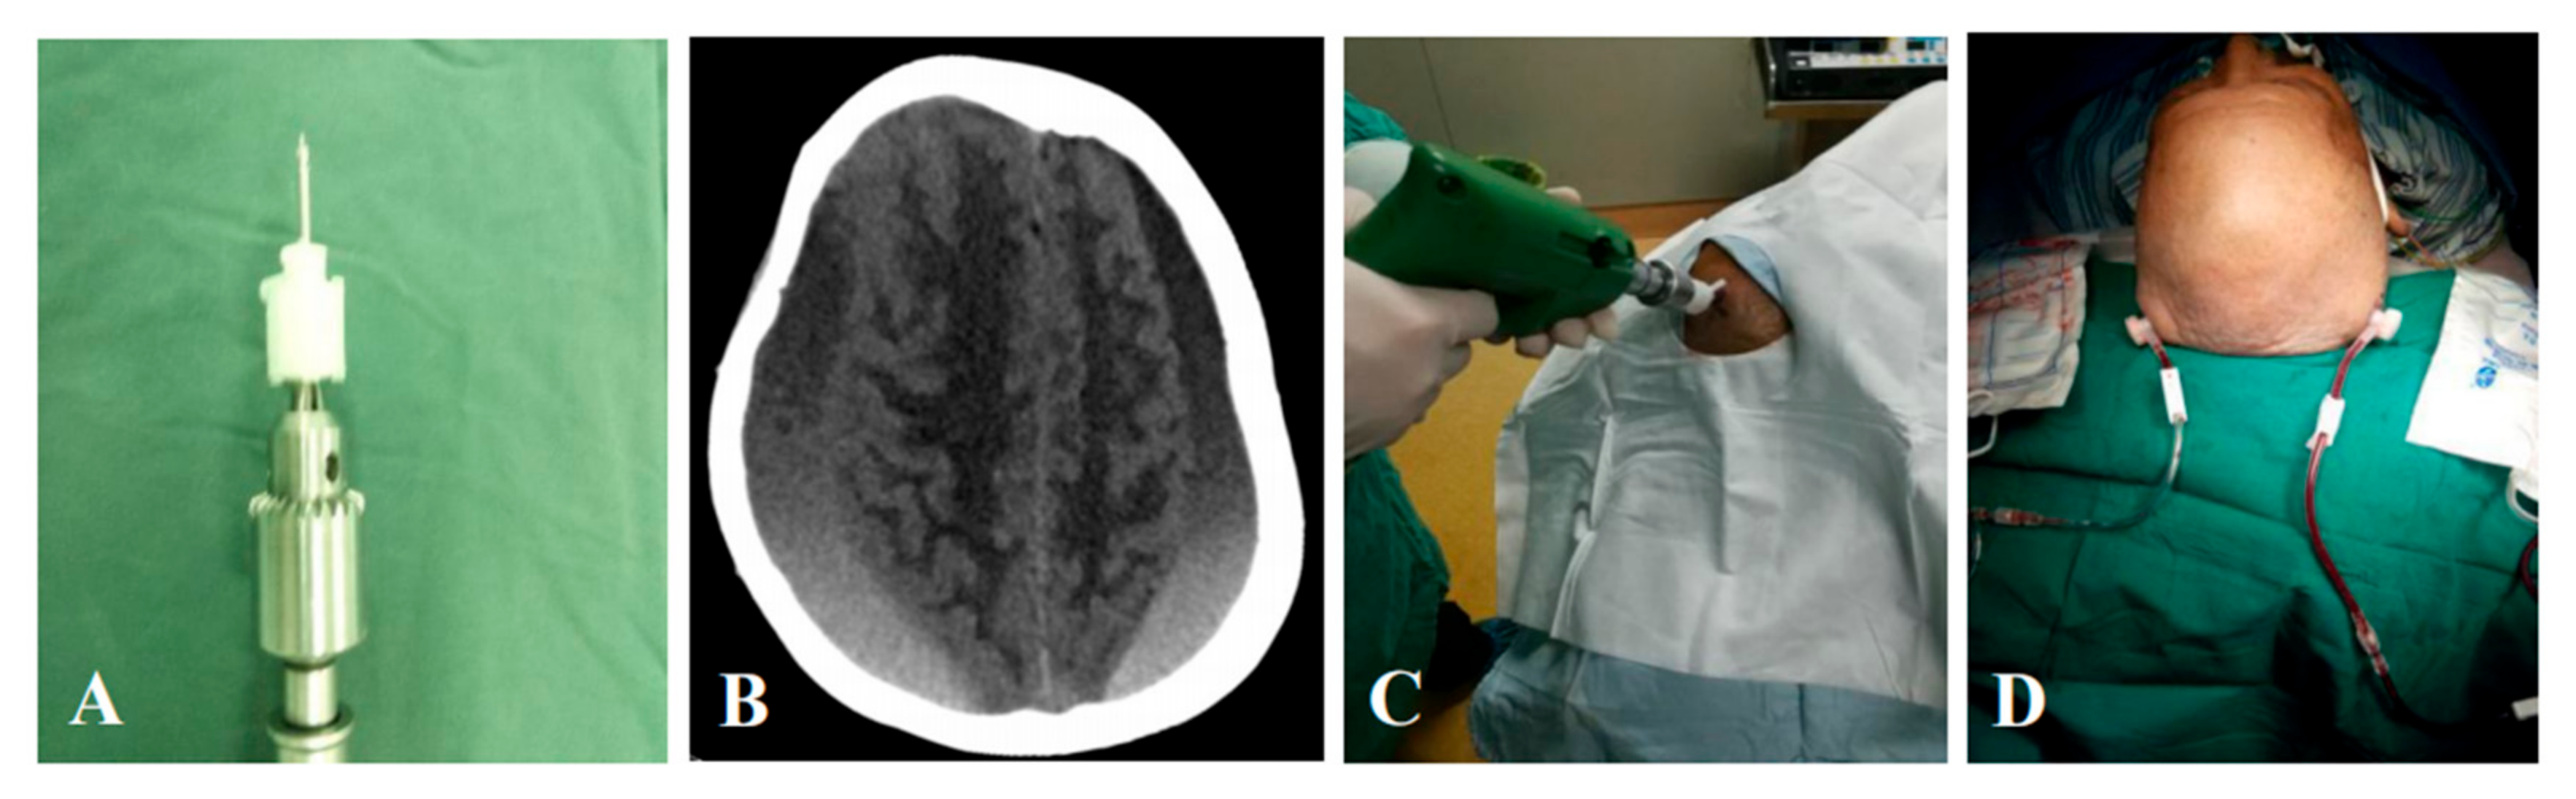

2.2. Hospitalized Flow and Surgical Procedure